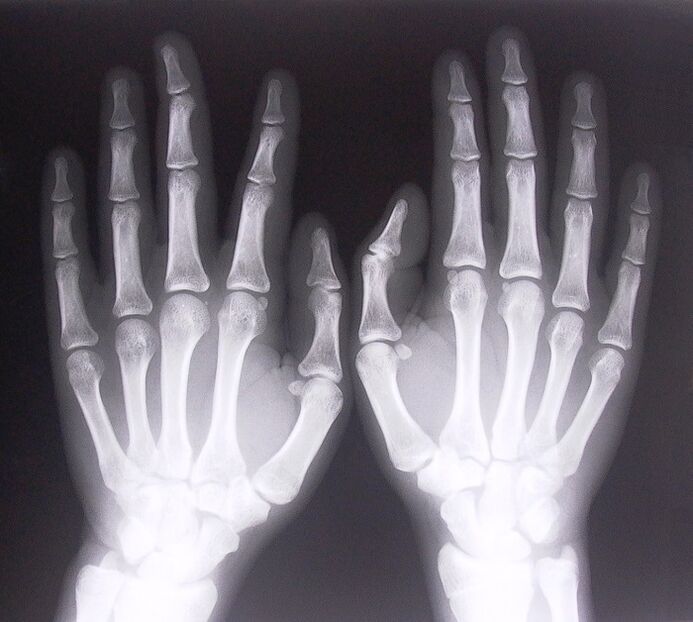

- Stenosis ligamentitis.X-ray is necessary to determine the cause of the disease.Symptoms are typical: painful movement of the hand, bending of the stretched hand.Also, during expansion, clicks are usually heard.

To start the treatment of pain in the finger joints, you need to correctly determine what disease caused them.To determine what kind of disease a person is suffering from who feels pain in the joints when bending the arms, doctors recommend to undergo the following procedures:

- Take an X-ray.